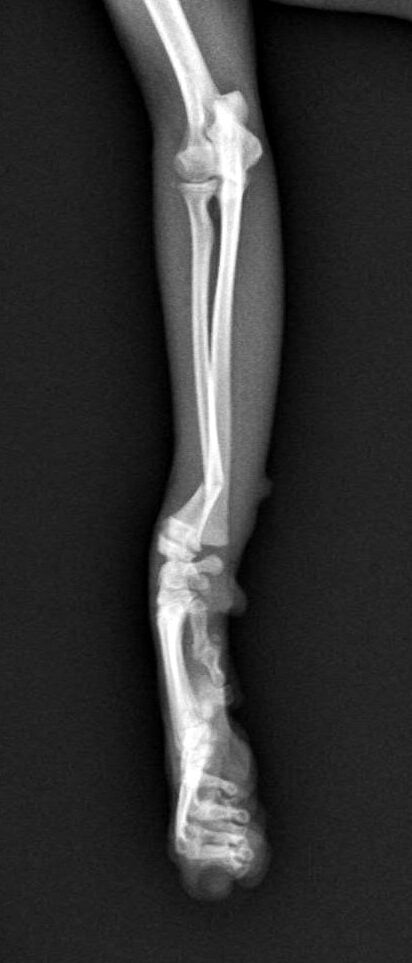

5~6歳以上の去勢手術をしていないオス犬に多い病気ですが、メス犬や去勢した犬に起こることもあります。お尻の筋肉が萎縮した結果、筋肉の隙間から直腸や膀胱が皮膚の下にとびでてしまいます。これにより便が出にくくなったり膀胱炎になったりします。手術をすることで機能回復および今後の致死的な状況を回避することができます。当院では去勢手術→結腸固定→前立腺固定→骨盤隔膜構成筋の縫縮→内閉鎖筋フラップ→浅臀筋フラップの順で通常腹側・臀部左右両側同時に行います。また老化以外に、筋肉が萎縮する原因があったり、腹圧がかかる原因があったりする場合も多いので、再発防止のためそれらの診断・治療も重要です。今回のワンちゃんも無事手術も終わり元気に退院しました。よかったね。